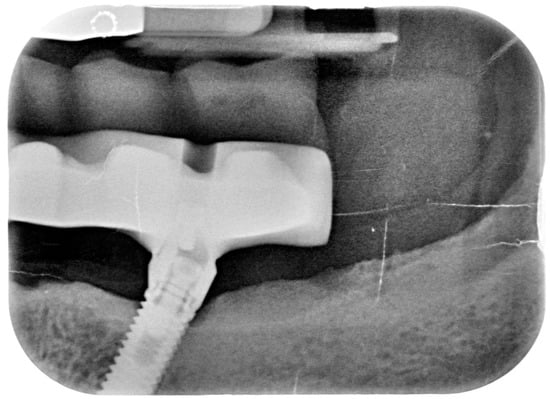

Bidimensional radiographic assessment of the lower jaw implants (with periapical and panoramic radiograph) was done. In the lower jaw, a concave bone resorption of about 2.5 mm mesial and distal to both distal implants were observed, and there was no bone resorption in two central implants (Figure 13 and Figure 14).

Figure 13.

X-ray of 3.5 dental implant in patient in 6 months after treatment.

Figure 14.

X-ray of 4.5 dental implant in patient in 6 months after treatment.